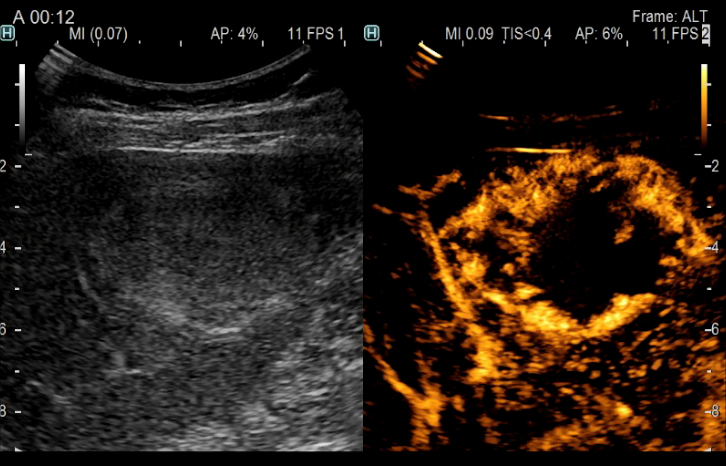

Aplicación: Abdomen

Función/análisis: CHI

Comentarios: Hígado